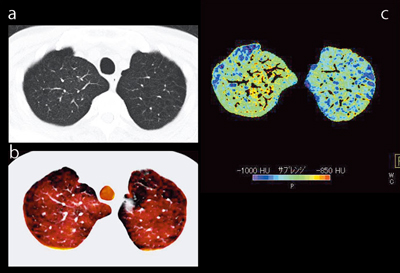

図1は,健常ボランティア(a)と肺気腫患者(b)のXeイメージである。黄色で示されるXeの分布は,aは均一だが,bはまだらであり,特に末梢での分布が少ないことがわかる。

図1 Xeイメージ

健常ボランティア(a)と肺気腫患者(b)の比較